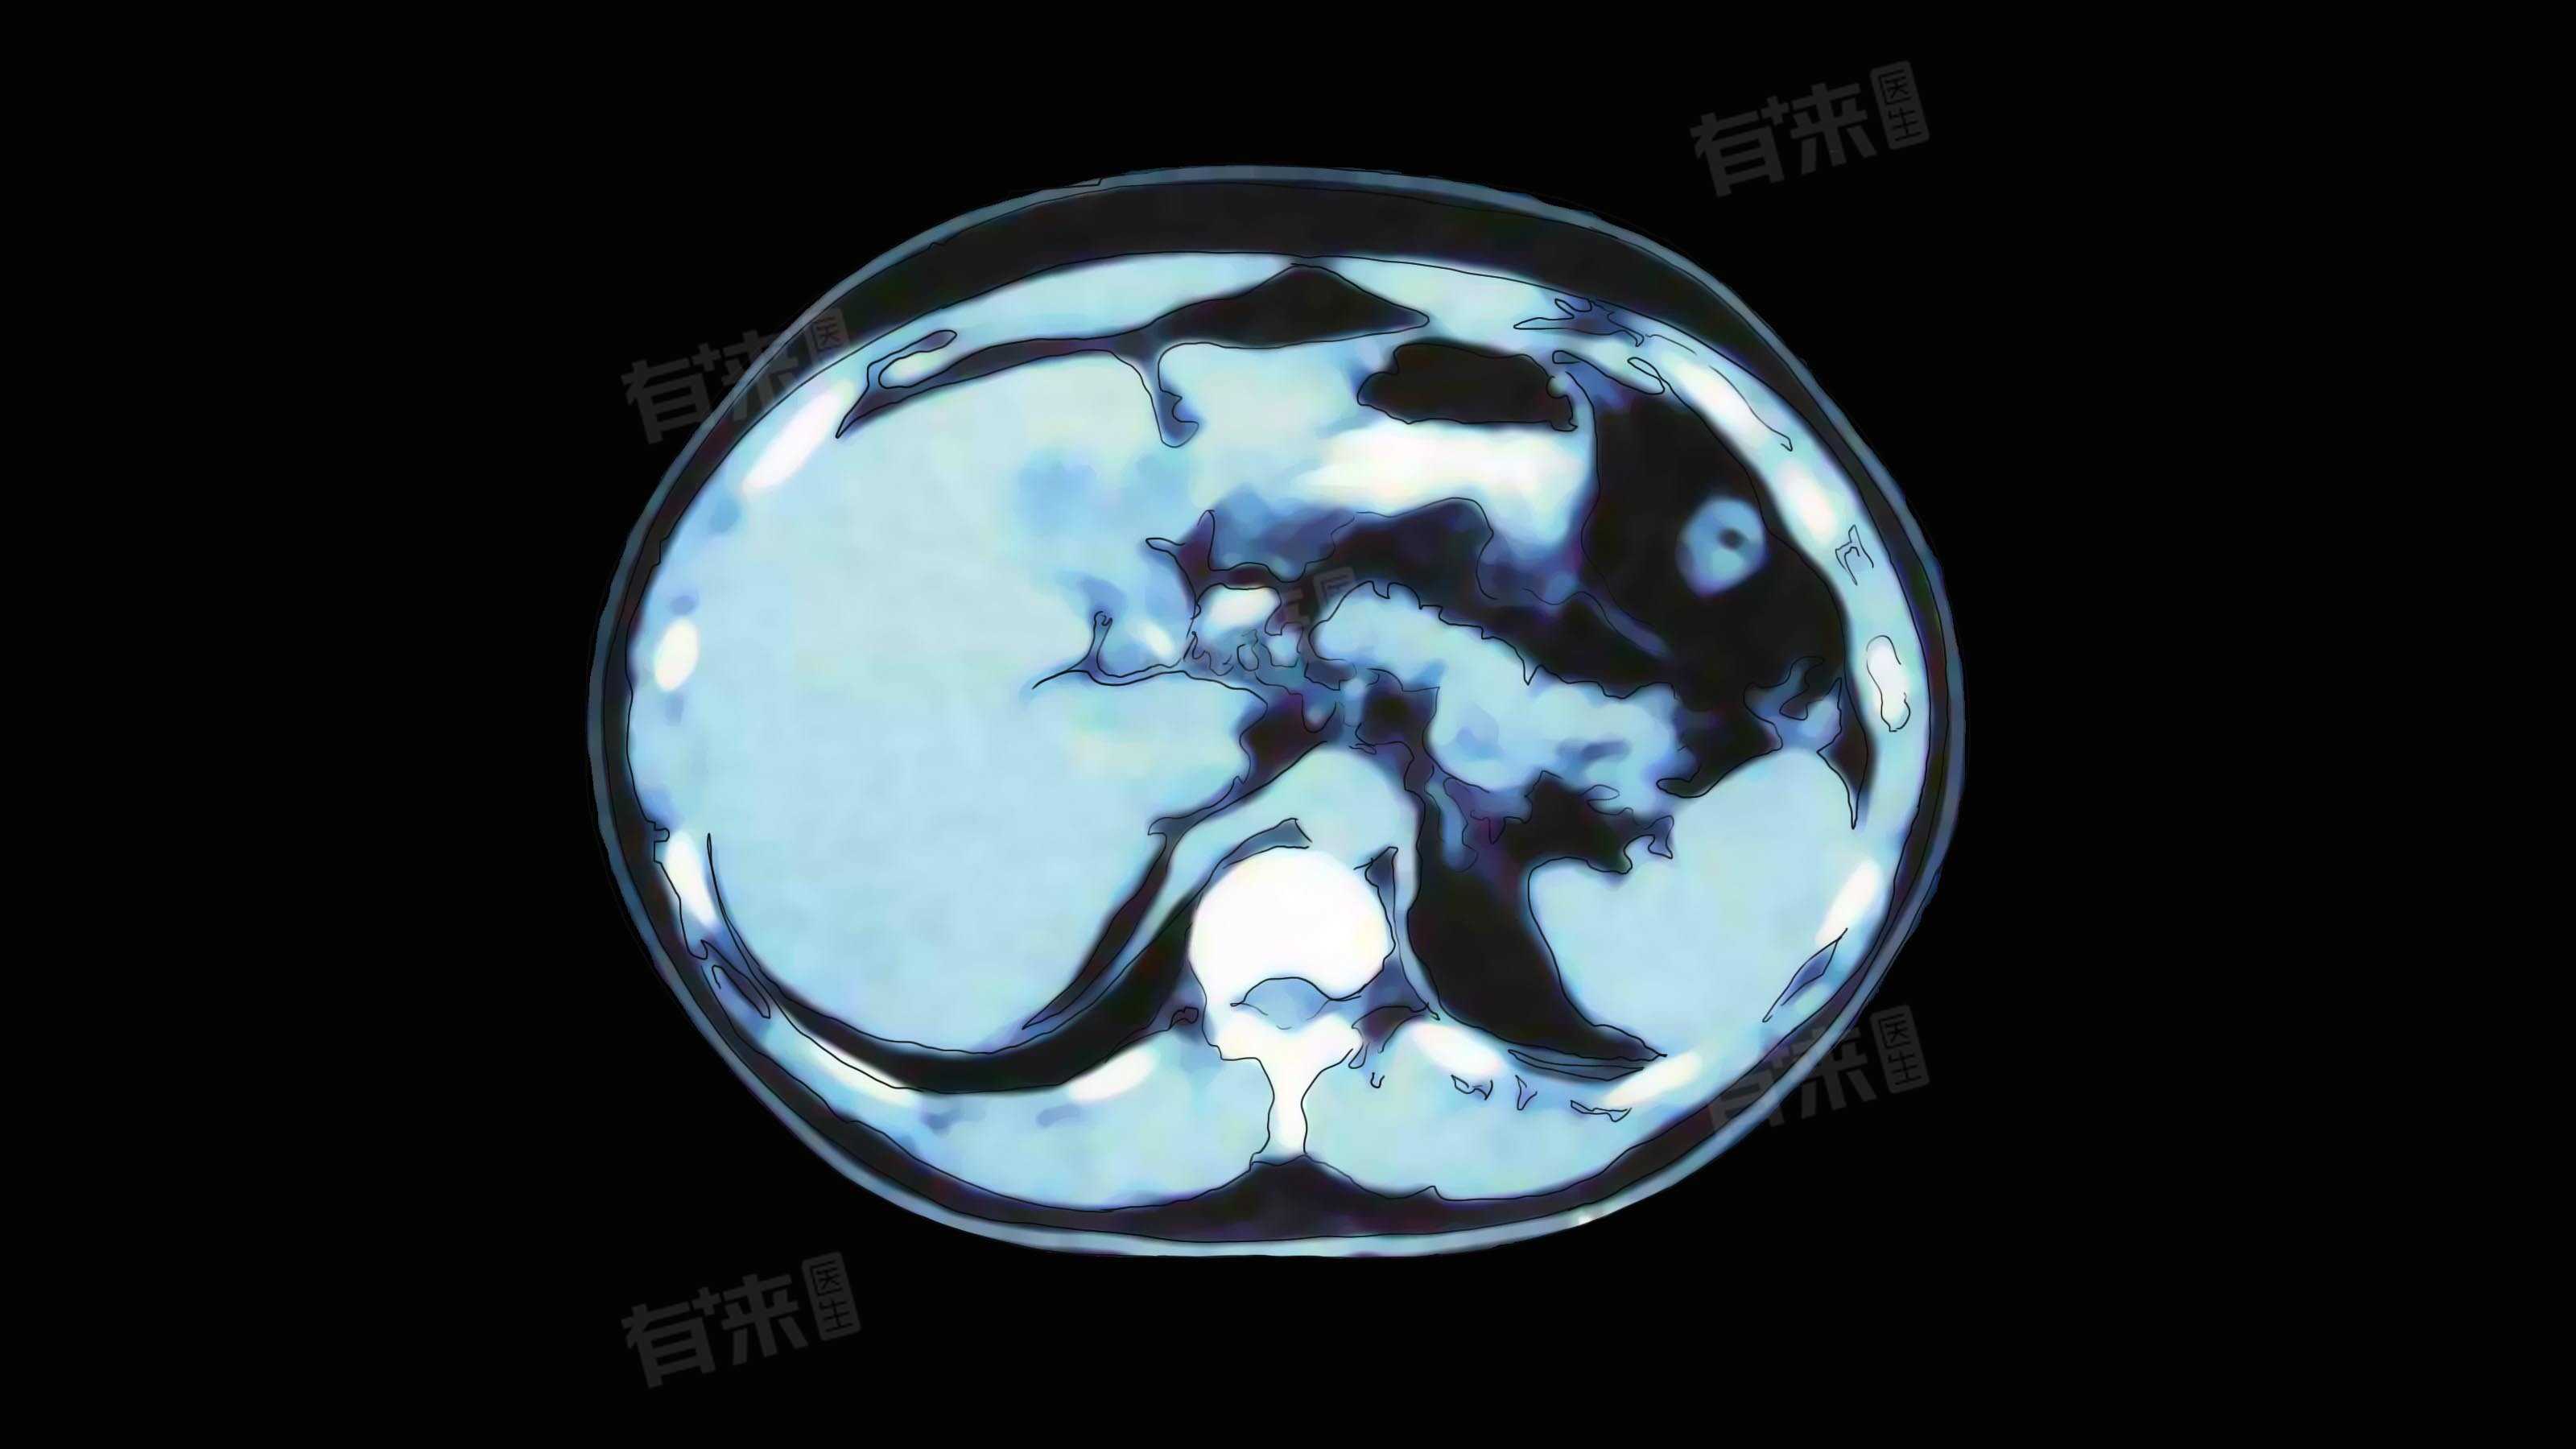

- CT图像是通过不同组织对X射线吸收程度不同而呈现出不同灰度,一般来说,骨骼在片子上显示为白色或灰白色,因为骨骼密度高,对X射线吸收多,脂肪组织呈黑色或深灰色,其密度较低,肌肉、脏器等软组织则呈现出中等灰度。如果某个区域的灰度与周围组织明显不同,可能提示存在病变。

- 熟悉人体正常解剖结构在CT片子上的表现是关键,比如,在颅脑CT中,要能分辨出大脑的不同脑叶、脑室、脑沟等结构;胸部CT可识别出肺组织、心脏、大血管等;腹部CT要认识肝脏、胆囊、胰腺、脾脏、肾脏等脏器的形态和位置。

- 一旦发现某个解剖结构的形态、大小、位置出现异常,就要高度警惕。例如,肝脏体积增大或缩小,或者发现原本不该存在的占位性病变,都可能是疾病的信号。

- 若发现异常区域,要进一步观察病变的特征。包括病变的形状,是圆形、椭圆形、不规则形等;边界是否清晰,清晰的边界提示病变可能相对局限,而模糊的边界可能意味着病变具有浸润性;病变的大小,可通过片子上的标尺测量,了解病变的范围。

- 还要注意病变内部的密度是否均匀,是否有钙化、液化等表现。比如,肺部的孤立性结节,若边界清晰、密度均匀,可能是良性结节;若边界有毛刺、内部密度不均,就要考虑恶性肿瘤的可能。